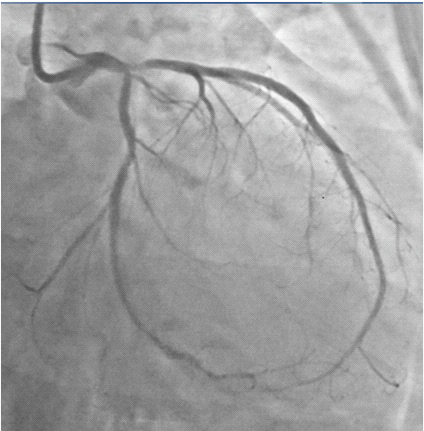

Figure 11 Fully expanded ( angiographically) stents in LM-LAD and LCX arteries, with TIMI 3 flow and no dissection.

Figure 12 Fully expanded LM-LAD and LCX stents with brisk TIMI 3 ante grade flow in both arteries.